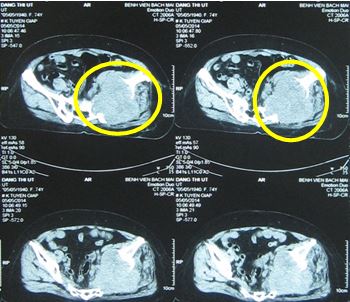

• Chụp cắt lớp vi tính vùng khung chậu: hình ảnh khối u kèm hủy xương chậu trái và phần mềm lân cận kích thước 9x10 cm, ngấm thuốc mạnh sau tiêm, xâm lấn khối cơ mông trái, cơ thắt lưng chậu trái, theo dõi tổn thương thứ phát (hình 1, vòng tròn đỏ).

Hình 1. Hình ảnh hủy xương chậu trái và phần mềm lân cận kích thước 9x10 cm, ngấm thuốc mạnh sau tiêm, xâm lấn khối cơ mông trái, cơ thắt lưng chậu trái (vòng tròn đỏ).